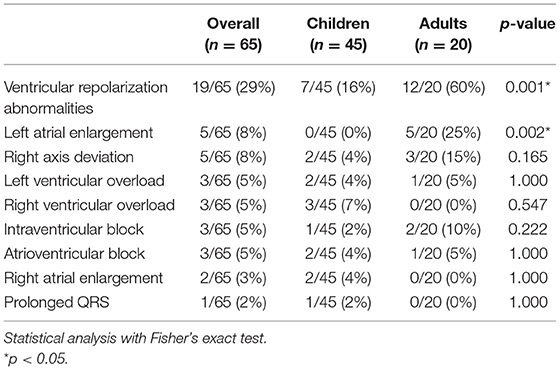

Electrocardiograms were performed in 65 patients (45 children and 20 adults) at some point during follow-up. All patients had a sinus rhythm, although transient junctional rhythm was observed for one female with MPS IVA in the middle childhood. The most frequently observed finding was the presence of repolarization anomalies (29%) (Table 5; Figure 4A). Left ventricular hypertrophy (LVH) and left atrium enlargement were present in 5 and 8% of the patients, respectively. Atrioventricular block and long QT intervals were also occasionally observed (Figure 4C), as well as intraventricular blocks. As compared to children, adults had a higher prevalence of most of the ECG abnormalities (Table 6), particularly ventricular repolarization abnormalities (Figure 4A) and left atrial enlargement (Figure 4B).

Table 5. Prevalence of electrocardiographic abnormalities at the last available electrocardiogram, including both ERT treated and untreated subjects.

Table 6. Prevalence of abnormalities in the resting electrocardiogram in children and adults with MPS.